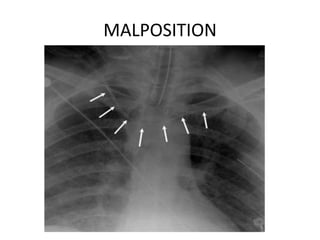

MALPOSITION